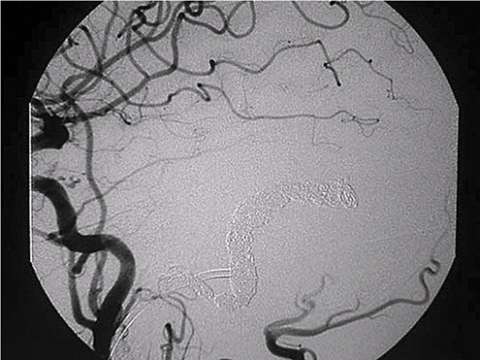

First step of the treatment is to obtain an entire picture of a DAVF and characterize it. Cerebral angiography (dye injection into brain arteries through a plastic tube) is the gold-standard and the most accurate way to do so. Based on the finding of cerebral angiography and the symptoms, the following options are offered:

- Endovascular embolization

One of the most worrisome finding is so called "cortical venous reflux". This is the sign that blood flow return to the brain is compromised and associated with high risk of brain hemorrhage. Regardless of the symptoms, DAVF's with cortical venous reflux should be treated as soon as practical by either endovascular embolization or open surgery. Recently, most DAVF's can be treated by endovascular embolization.

When a patient cannot tolerate the symptom such as pulsating noise, endovascular embolization is considered. Simple observation can be an option for some DAVF's with negligible risk of hemorrhage.